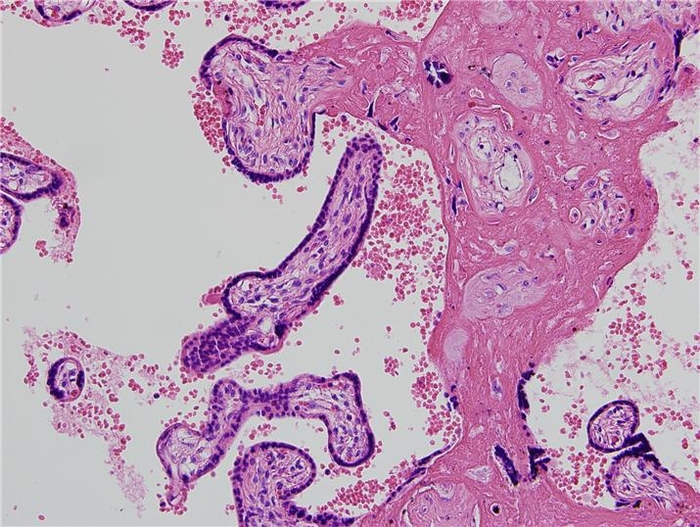

제목: 넝마주이 (2014)

조직소견: 태반

작품설명: 등에 망태기를 둘러메고 집게를 사용하여 쓰레기 속에서 보물을 찾고 있다.